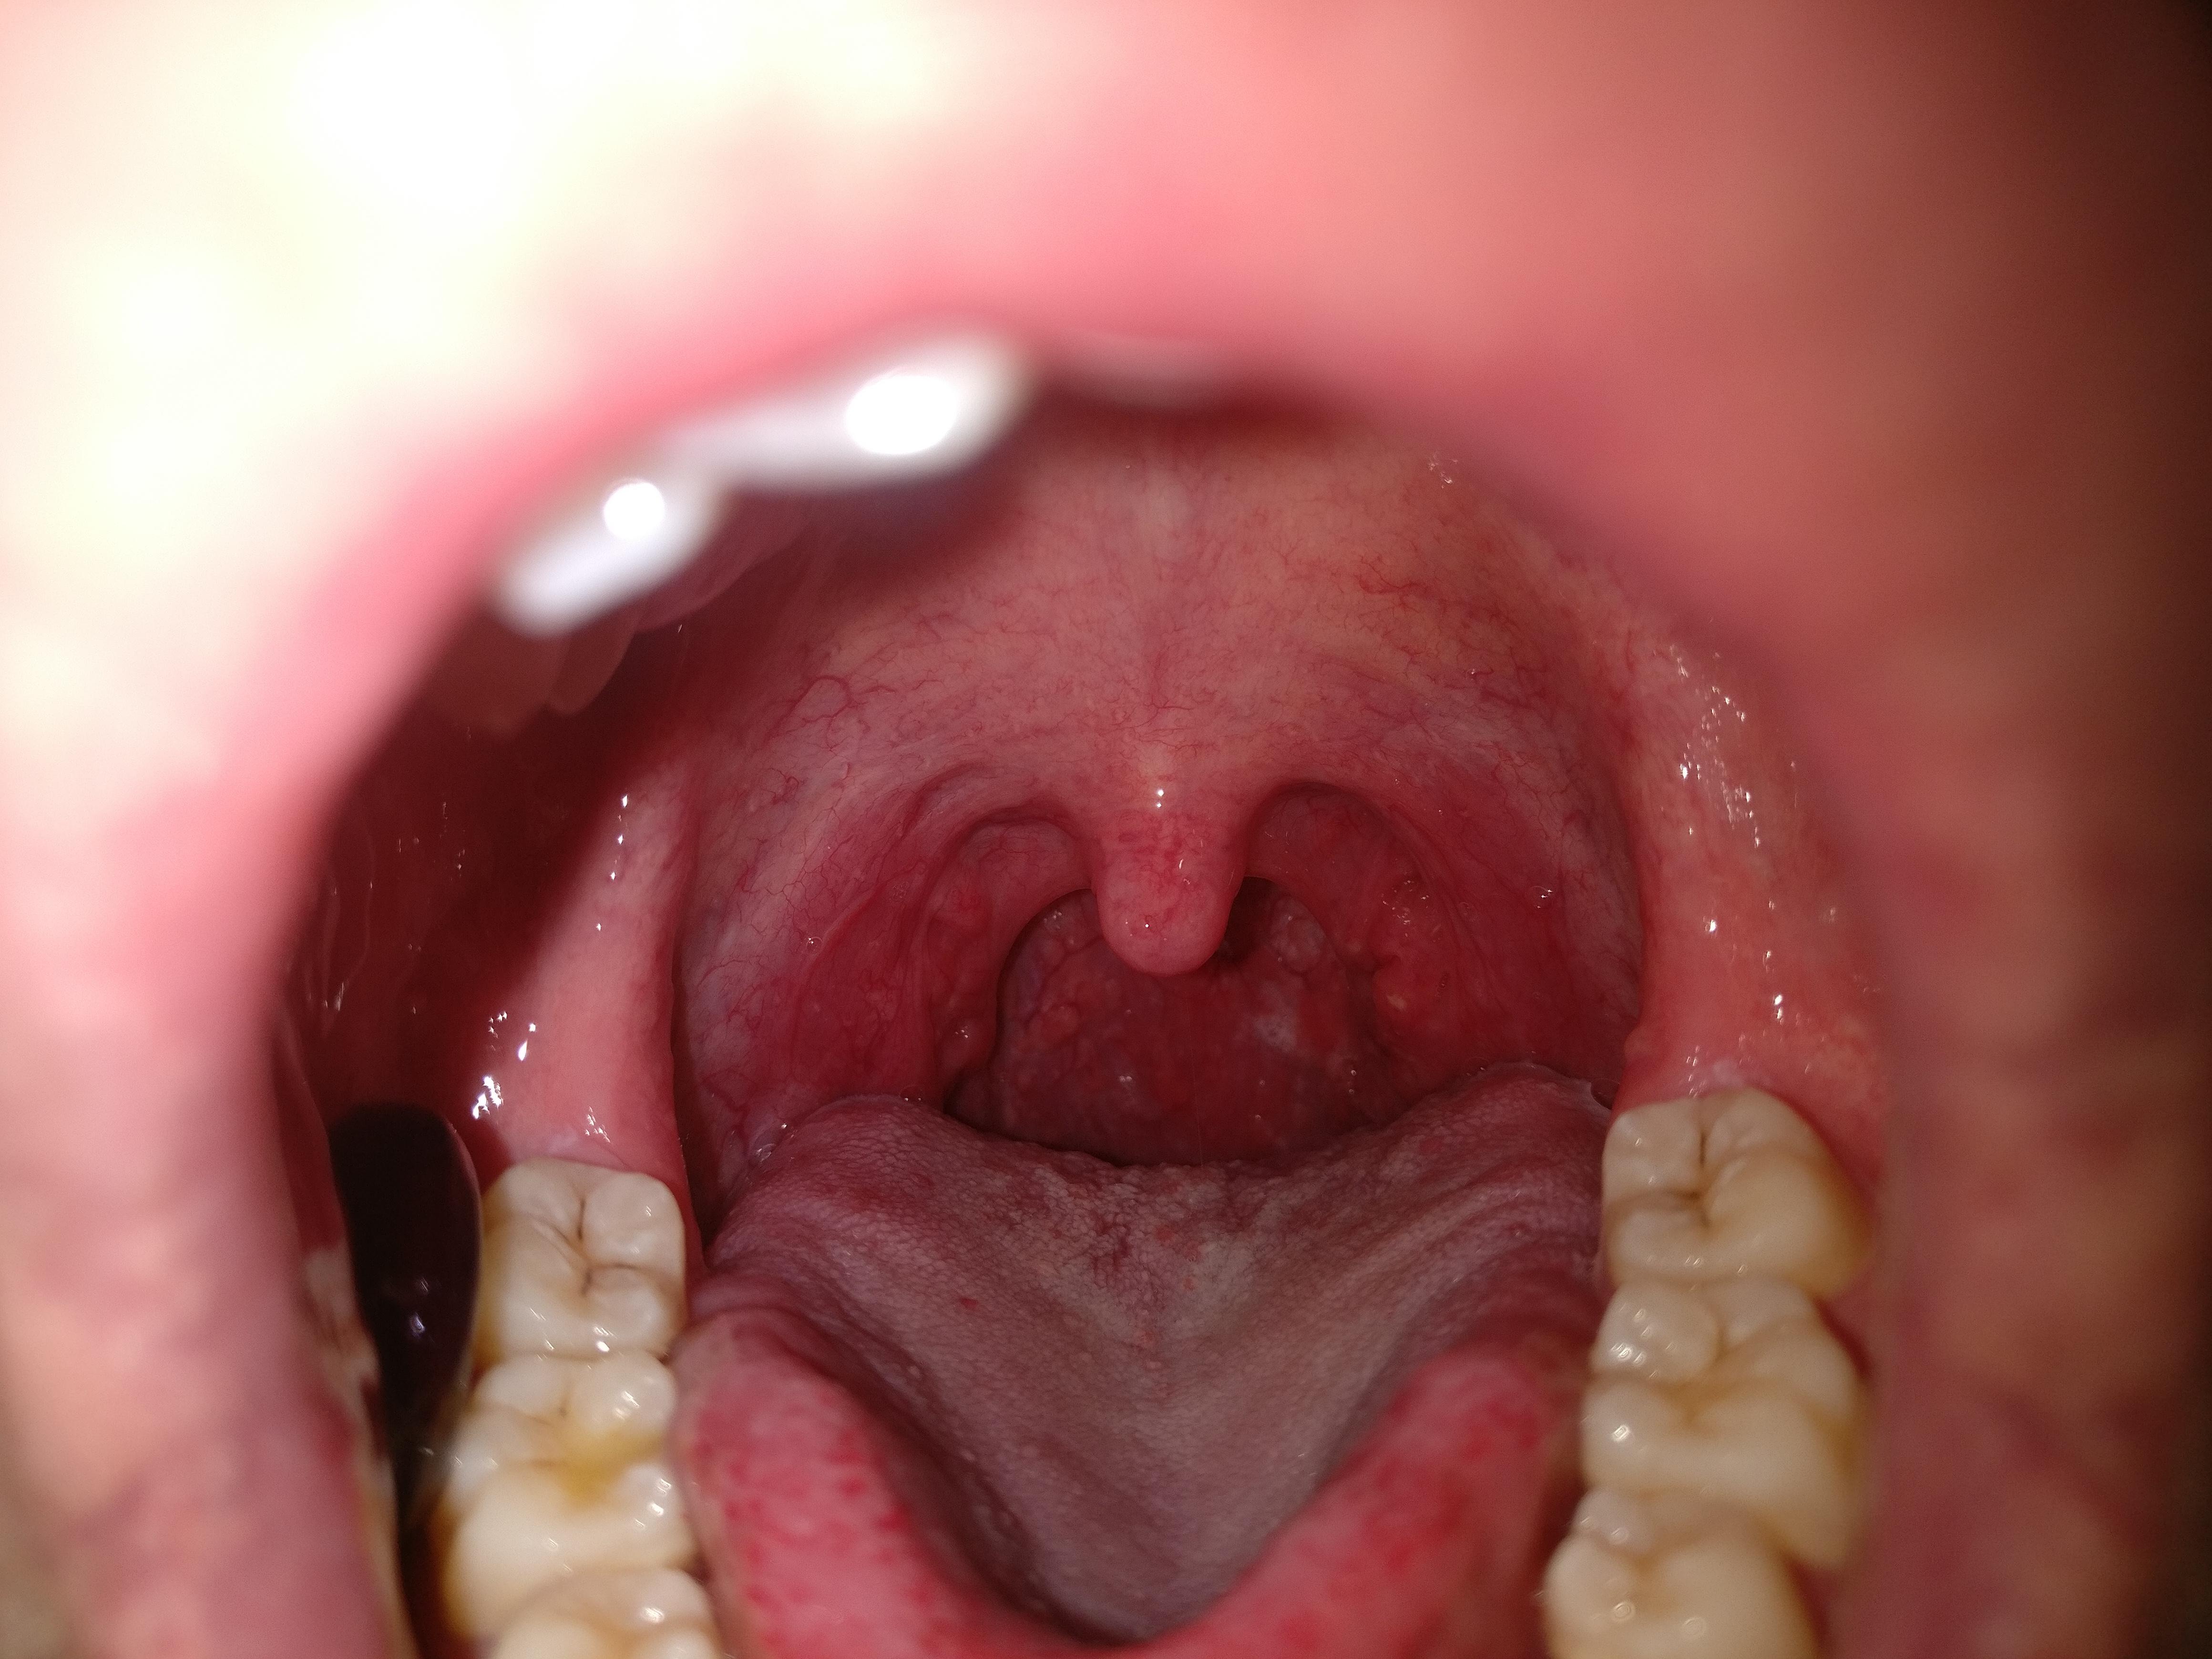

Nasal Endoscopy Procedure & What It Is Why Is My Nasal Spray Dripping Down My Throat As the mucus builds up, it can make you feel congested or. Most products can be applied while you’re in an upright position, so you don’t have to tilt your head back. Drainage in your throat, or postnasal drip, is when the glands in your nose and throat continually produce mucus to filter out the nasal passage and provide lubrication.. Why Is My Nasal Spray Dripping Down My Throat.